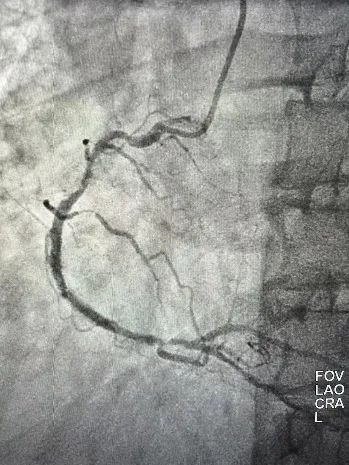

患者男性,63岁,既往糖尿病肾病,慢性肾功能不全规律血液透析,RCA曾行PCI。本次因为心力衰竭入院,入院后超声提示左室EF 仅有24%,伴有中量二尖瓣反流,冠状动脉造影提示:右优势型,血管走行区可见重度钙化影,LAD 中段次全闭塞,LCX近端重度狭窄;RCA支架内再狭窄,支架近端及远端均存在重度狭窄。患者拒绝CABG,遂在IABP的支持下,首先处理LAD。本次择期处理RCA病变,由于RCA近端血管钙化迂曲,IVUS探头无法通过,遂在延伸导管的支持下,直接进行Shockwave IVL(3.5mmX12mm)治疗,在经过8个周期80个脉冲对RCA多处靶病变进行充分预处理后,以药物洗脱支架联合药物洗脱球囊的方式顺利完成RCA的血运重建。目前患者EF由24%上升至43%,心衰症状明显缓解。

图3:支架联合药物洗脱球囊治疗后